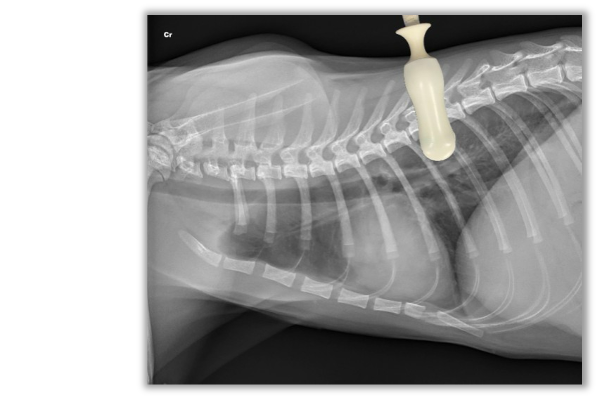

Técnica “localización tubo torácico” (CTS)

Útil para evaluar:

Neumotórax, aire libre en la cavidad pleural, ya que el aire asciende y es la ubicación más alta sobre la cavidad pleural.

A continuación puedes ver una imagen y vídeo ilustrativos sobre cómo y donde posicionar la sonda ecográfica: